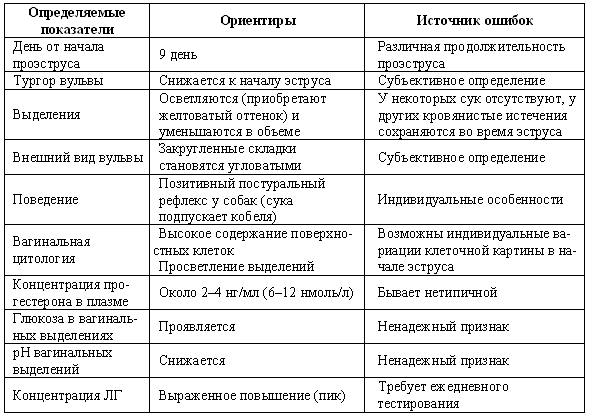

После составления анамнеза можно будет сформулировать текущую проблему как:

• отсутствие проявлений эструса;

• бесплодие, сопровождающееся отклонениями в цикле (короткий интервал интер-проэструса, короткий проэструс, затяжной проэструс/эструс);

• бесплодие на фоне, очевидно, нормального эстрального цикла;

• неспособность к вязке или самопроизвольное прерывание беременности.